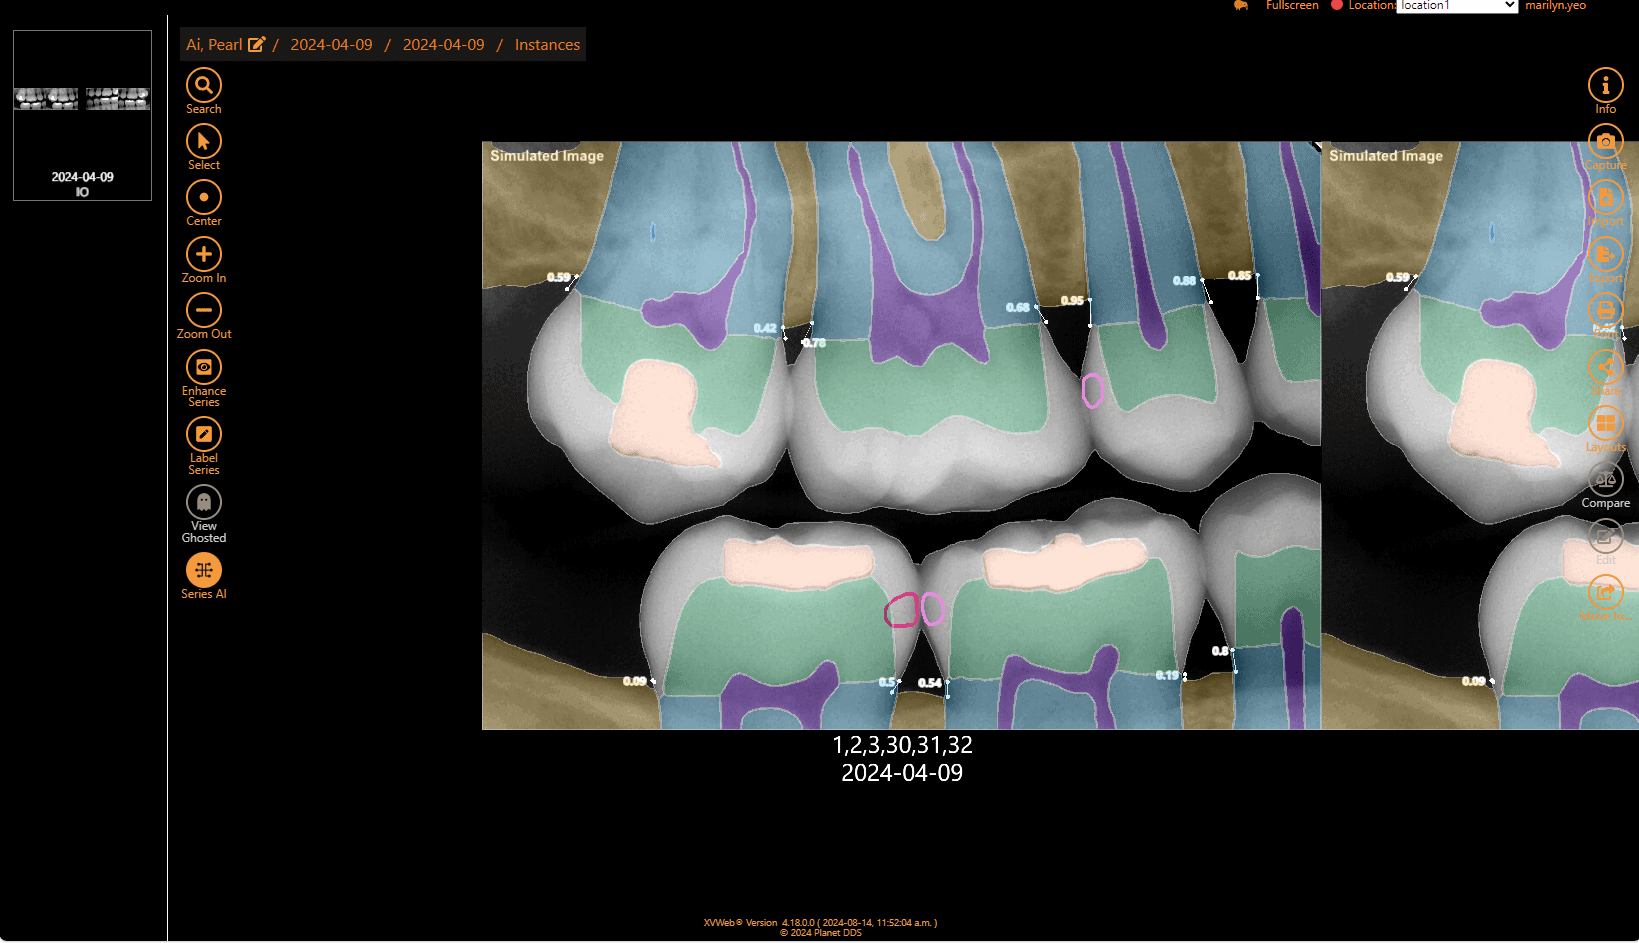

Get a second opinion to quickly detect decay, identify tartar buildup, and assess bone levels, ensuring a more accurate diagnosis of periodontal disease.

Within minutes, have more data than ever to guide and support your diagnosis with the patient chairside. AI makes it easier to visualize the areas of concern so patients can make a more informed decision.